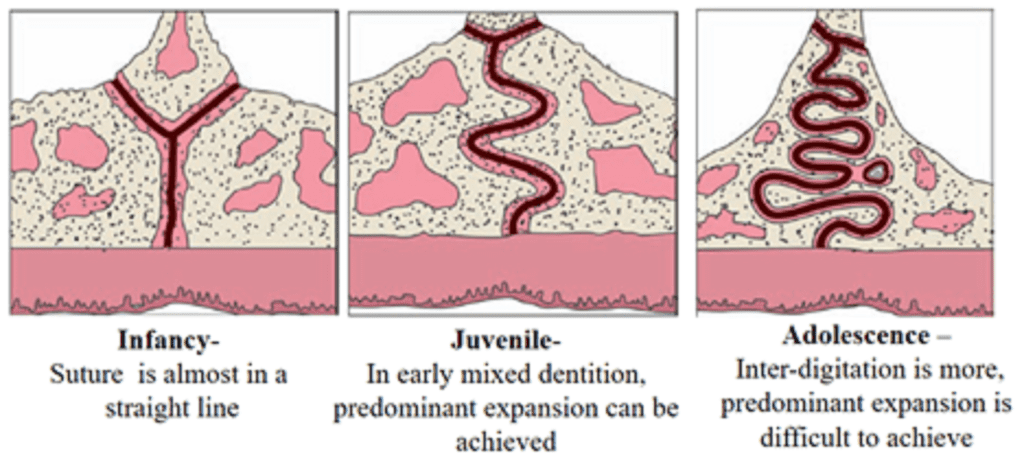

Sutures – Mid Palatine Suture plays a key role in Maxillary expansion

Infancy – Y-shape, Juvenile – T-shape, Adolescence – Jigsaw puzzle

Normal palatal growth is completed by age of 6. Increasing interdigitation of the suture makes separation difficult to achieve after puberty.